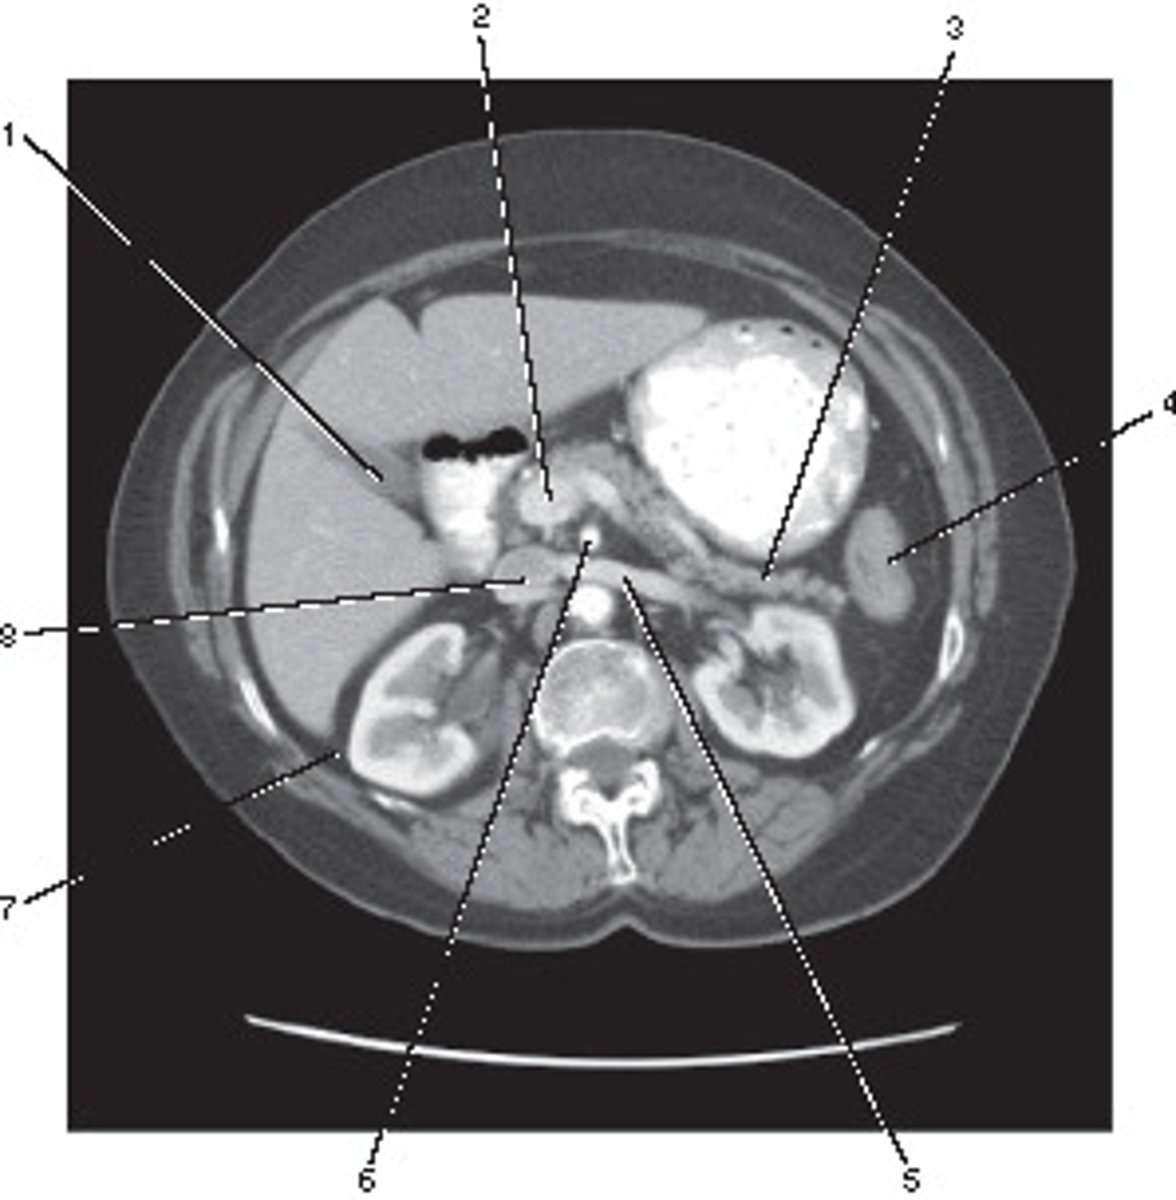

Aorta

Number 2 corresponds to which of the following?

<p>Number 2 corresponds to which of the following?</p>

Inferior Vena Cava

Number 8 corresponds to which of the following?

<p>Number 8 corresponds to which of the following?</p>

Spleen

Number 4 corresponds to which of the following?

<p>Number 4 corresponds to which of the following?</p>

IV only

On the basis of the appearance of this image, what contast media was utilized?

<p>On the basis of the appearance of this image, what contast media was utilized?</p>

Number 6 corresponds to which of the following?

<p>Number 6 corresponds to which of the following?</p>

9

Ureter

Stomach

Number 1 corresponds to which of the following?

<p>Number 1 corresponds to which of the following?</p>

Psoas Major Muscle

Corticomedullary;

30-40 seconds after injection,

the corticomedullary phase demonstrates optimal enhancement of the renal cortex with maximum differentiation from the renal medulla

This image of the abdomen was most likely acquired in which in which renal enhancement phase?

<p>This image of the abdomen was most likely acquired in which in which renal enhancement phase?</p>